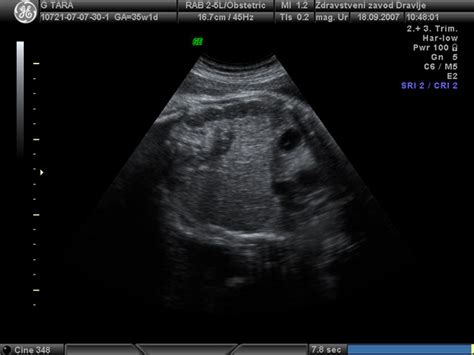

Za spremljanje količine plodovnice se uporabljajo različne metode, med katerimi je najpogostejši ultrazvočni pregled. Z ultrazvokom se lahko oceni globina najglobljega žepa plodovnice (DP) ali izračuna indeks plodovnice (AFI), ki predstavlja seštevek globine štirih žepov v vseh kvadrantih maternice. Kot normalne vrednosti AFI veljajo med 8 in 18 centimetri. Vrednosti med 8 in 12 cm pogosto štejejo za blag hidramnij, od 12 do 15 cm za zmeren, nad 15 cm pa za hud hidramnij.